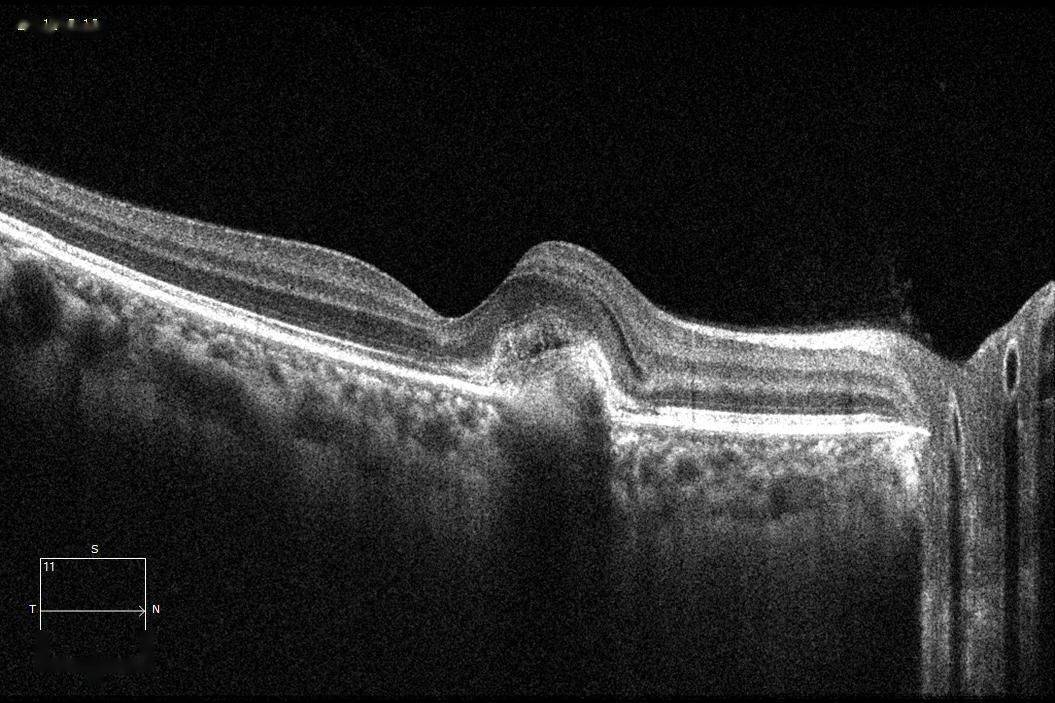

每周最佳病例分享 | 从一个cnv说起

图片尺寸1055x703

病理性近视cnv的定义及治疗的新进展总结 (转载)

图片尺寸466x610